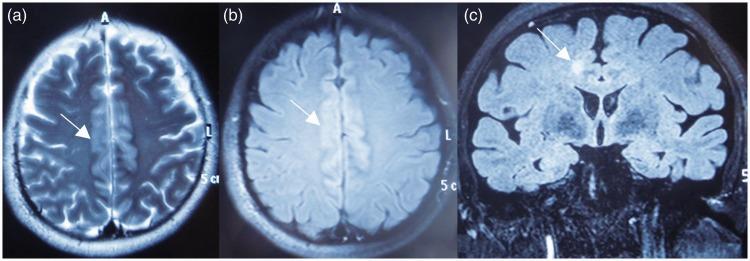

Magnetic resonance imaging (MRI) is recommended for patients with epileptic seizures to rule out an underlying focal lesion. However, the radiological characteristics of epilepsy are not well elucidated. Transient periictal MRI abnormality (TPMA) refers to reversible MRI signal changes observed in epileptic patients. A 32-year-old man presented with a 2-week history of epileptic seizures, which initially manifested as focal aware seizures and progressed to a generalized tonic-clonic seizure on the third day. Electroencephalography showed sharp waves, sharp and slow wave complexes, and irregular δ waves over bilateral temporal lobes. After admission, brain MRI showed abnormal signals in the bilateral frontoparietal lobes. He was administered oral oxcarbazepine (75  mg twice daily). During follow-up he was seizure-free; the abnormal MRI signals persisted at 2 weeks, but were completely resolved at 4 months. The possibility of TPMA should be considered in patients with epileptic disorders, and differentiated from a potential epileptogenic lesion.

对于癫痫发作患者,建议进行磁共振成像(MRI)以排除潜在的局灶性病变。然而,癫痫的放射学特征尚未得到充分阐明。发作间期短暂性MRI异常(TPMA)是指在癫痫患者中观察到的可逆性MRI信号变化。一名32岁男性,有2周癫痫发作史,最初表现为局灶性认知性发作,第三天进展为全面性强直阵挛发作。脑电图显示双侧颞叶有尖波、尖慢波复合波和不规则δ波。入院后,脑部MRI显示双侧额顶叶有异常信号。给予口服奥卡西平(每日两次,每次75毫克)。随访期间无癫痫发作;MRI异常信号在2周时持续存在,但在4个月时完全消失。癫痫患者应考虑TPMA的可能性,并与潜在的致痫性病变相鉴别。